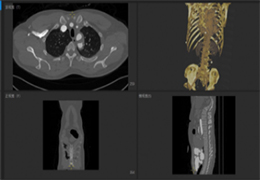

ANYTHINK 经导管主动脉瓣膜置换术分析系统